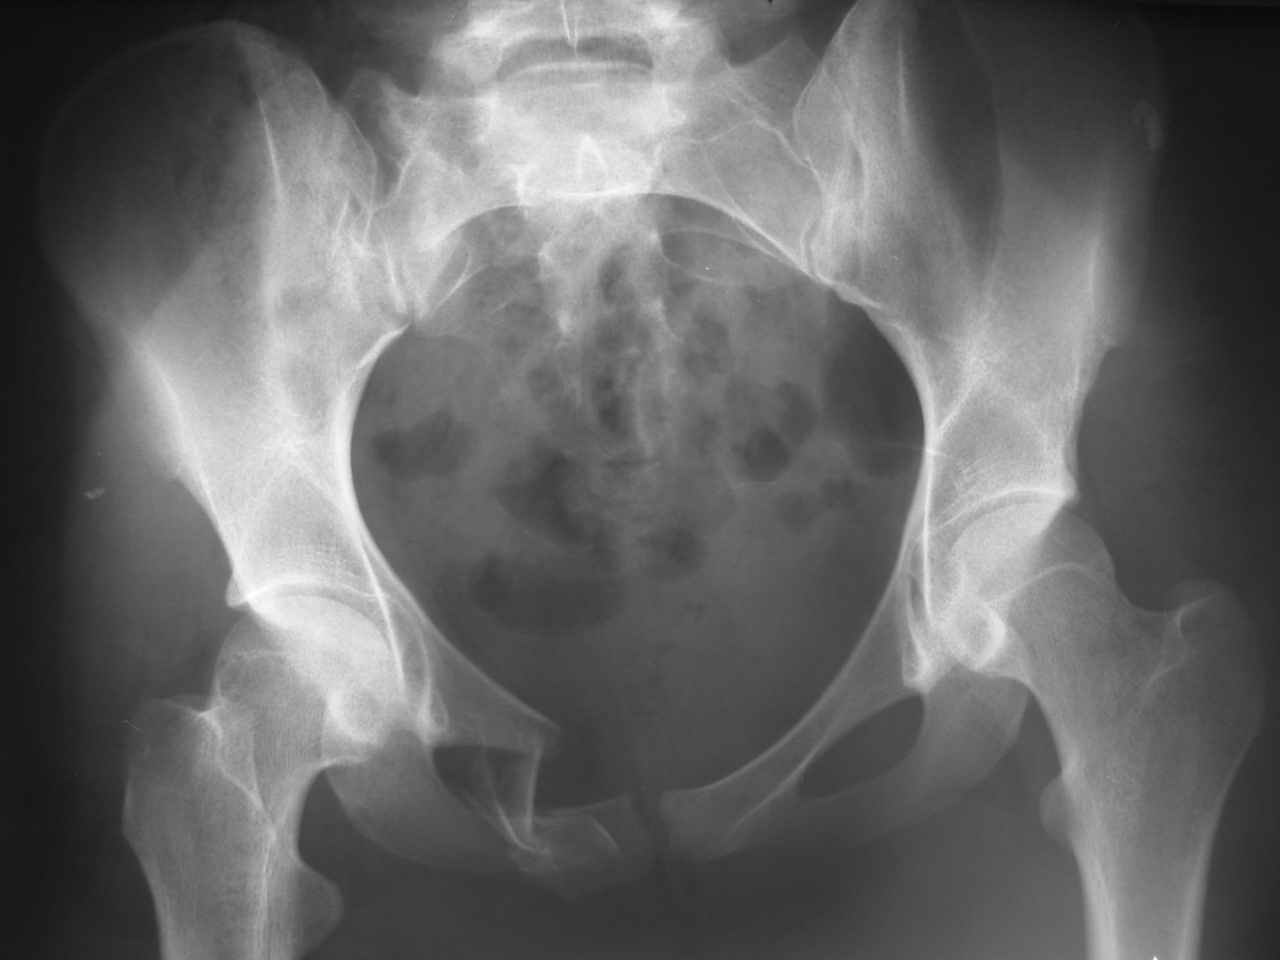

Уважаемые коллеги! К нам поступила молодая девушка 18 лет с оскольчатым переломом лонной и седалищной кости справа, после травмы прошел 1 месяц. Нужно ли вообще оперировать, стоит ли гнаться за анатомией? Или сделать комбинированный остеосинтез?

Надо бы начать с дополнительных проекций (хотя бы inlet), сделать КТ для уточнения повреждения задних отделов таза - виден перелом крестца. Здесь, похоже, ротационно нестабильное повреждение по механизму бокового сжатия. И вообще, Алексей, у тебя же есть экземпляр моей диссертации - читай на ночь ;-)

ЕЧ -Прямая проекция только не дает полной информации о характере повреждений заднего отдела. Судя по механизму травмы, задняя крестцово-подвздошная связка должна пострадать помимо видимого на Рг грамме трансфораминального перелома справа. КТ и инлет проекция были бы полезны.

В принцине анатомия - функционально обоснованное пространственное расположение образований, составляющих тазовое кольцо. Если внимательно присмотреться даже к этому снимку - можно выявить грубую деформацию, сравнимую со смещением по длине, ширине и под углом диафиза длинной трубчатой кости. Кроме того имеет место импрессионный перелом боковых масс крестца, ротационное смещение правой половины таза, грубое нарушение непрерывности костного остова по лобковой дуге с линейным и ротационным

смещением справа, некорректная установка головки правого бедра с вытекающими последствиями. Так что уж и не знаю надо ли гнаться за анатомией или физиологией или биомеханикой. При переломах бедра и голени этих вопрсов уже не возникает.

Проблема этой девушки не спереди а сзади в поврежденном крестцово-подвздошном сочленении с той же стороны. Судя по снимку есть смещение. Нужно сделать снимки на вход и выход таза (outlet, inlet) и стоит добавить КТ и тогда решить об операции. Судя по снимку девушка нуждается в вправлении и фиксации или артродезе крест-подвзд.